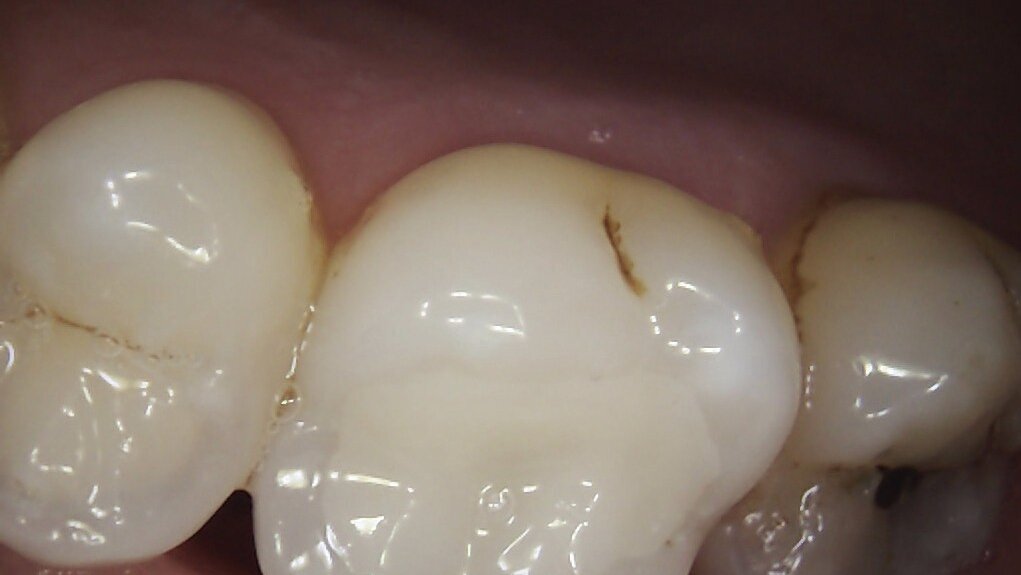

On examination, teeth 16 and 46 had amalgam restorations, with defective margins and signs of corrosion of the metal into the surrounding dentinal tubules. Tooth 46 had a vertical fracture running from occlusal surface to 1mm coronal if the gingiva on the palatal aspect. Neither tooth was tender to percussion and both scored positively with electric pulp testing. However, 46 did have pain on release when biting on the palatal cusps of the crack finder. The patient confirmed this was the sensation she had been experiencing over the last few months. Two periapical radiographs confirmed caries under each amalgam restoration but no evidence of periapical pathology.

I suggested removing each amalgam restoration and any stained dentine and fractures and restoring the teeth with Inlays fabricated by CAD/CAM system, MyCrown.